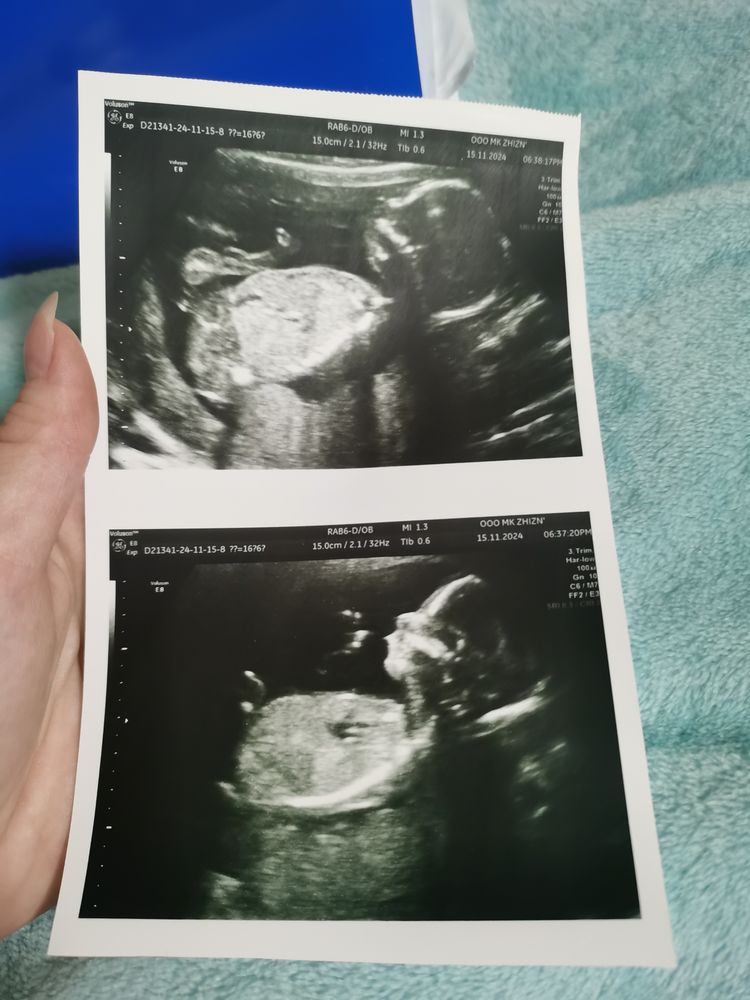

УЗИ 16 недель

УЗИ, КТГ, доплерПовидались с Креветкой на узи у другого врача 🙏

Безумно была рада слышать что все хорошо

УЗИст сказала, что расширение ТВП 2.9 это очень незначительно...

Единственное, за что теперь переживаю - врач сказала, что сокращен желудок у плода, и возможно он или я голодны

Какой замечательный малыш 🥰🙏🏼 растите здоровыми и красивыми ❤️

На счет желудочка -нужно экспертоное узи , переделай через время ❤️